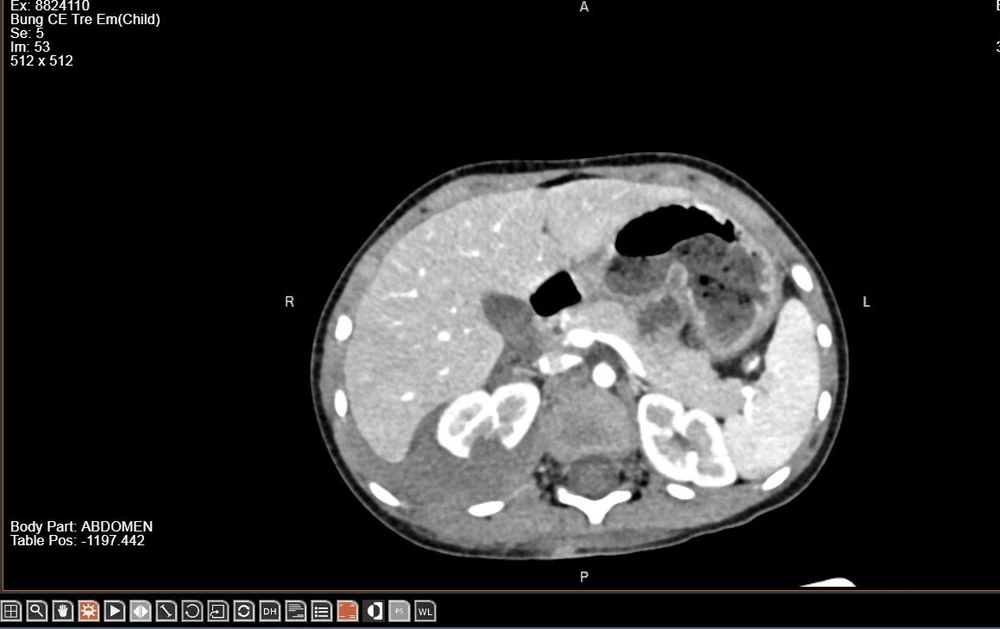

Trẻ được chỉ định thực hiện chụp cắt lớp vi tính ổ bụng có tiêm thuốc cản quang để đánh giá chính xác mức độ tổn thương thận. Kết quả cho thấy thận phải vỡ làm 2 mảnh, có thoát thuốc ra khoang quanh thận. Bác sĩ kết luận trẻ bị chấn thương thận phải độ IV.

Hình ảnh thận phải của bệnh nhi vỡ làm 2 mảnh trên phim chụp. Ảnh BVCC